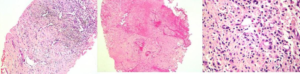

52 year old lady with right breast mass of recent onset.

What is the mass?

Clue: She is IDDM since 15 years